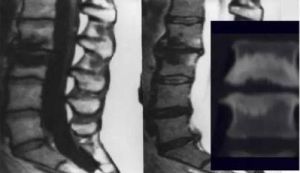

椎體終板骨軟骨炎,簡稱椎體終板炎。多由於椎間盤變性引起.引起椎體終板炎的原因有多種,如年齡、陳舊性外傷、無菌性炎症、長期服用激素等,椎板炎是無菌性炎症 外力損傷 退行性病變 骨結核造成的炎症 臨床表現腰疼 局部積液 可引起椎間盤炎症 黃韌帶萎縮 周圍組織炎等。

終板炎